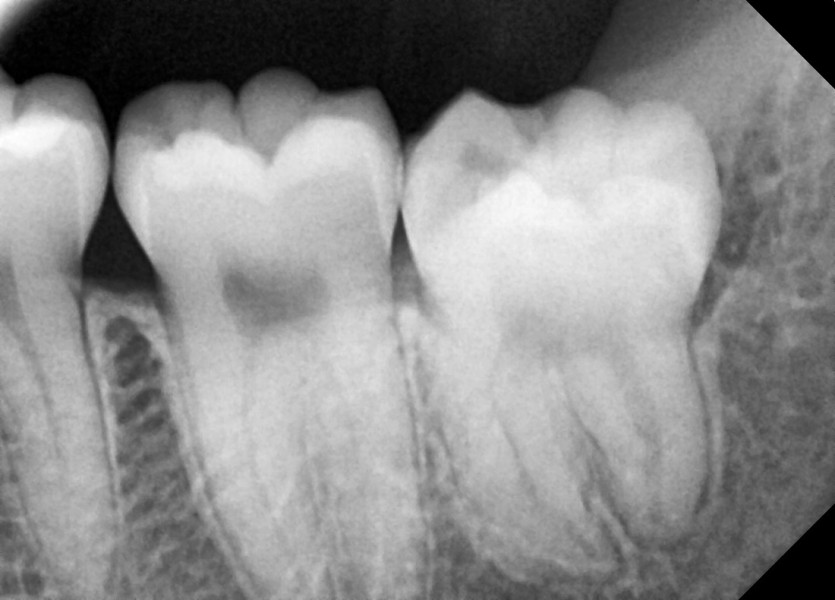

#18,28,38,48 사랑니 발치

구강 외과 전문의가 당일 발치했습니다.